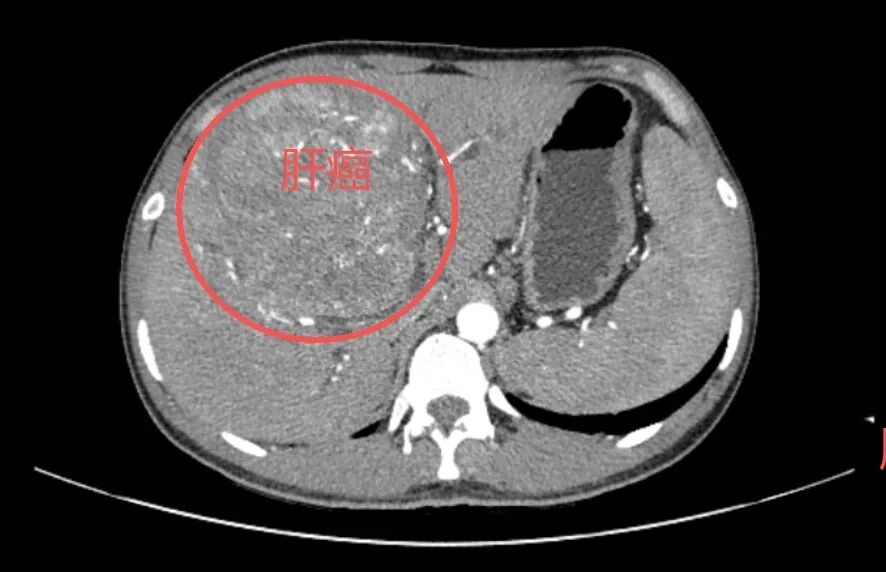

收治了一名年轻的肝癌晚期患者

25岁小王(化名)的CT检查报告上

“肝脏巨大肿瘤”等字样

10年前 还是初中生的小王 在体检中查出“乙肝表面抗原阳性” 他觉得自己年轻没当回事 从未规律复查 也没主动咨询过专科医生 直到近期 持续的乏力、腹胀缠上了他 检查报告上的“肝癌晚期” 如晴天霹雳 …… 小王的情况并非个例。据统计,2024一2025年,东莞市滨海湾中心医院院感染科已筛查出8例40岁以下的乙肝相关晚期肝癌患者,其中2例还未满30岁。这些患者的经历并非偶然,背后藏着大众对乙肝认知的普遍漏洞,最终将 “可防可控” 的慢性疾病拖成晚期癌症。 病毒性肝炎是全球重大公共卫生问题之一。在我国,乙型病毒性肝炎(简称“乙肝”)因高感染率、慢性化风险及严重并发症,成为威胁全民健康的重要挑战,其病毒主要通过血液、母婴和性接触传播。 认为“乙肝病毒携带者是‘健康携带者’不需要治疗”的观念已经过时了,2022版《慢性乙型肝炎防治指南》早已用“慢性乙肝病毒携带状态”,取代了“健康携带者”这个说法。 乙肝病毒感染,更像是一种需要终身管理的慢性健康状况,并非不可控的“洪水猛兽”,别再轻信“健康携带者”的旧说法,也别再用“年轻”“没症状”,当借口忽视它。